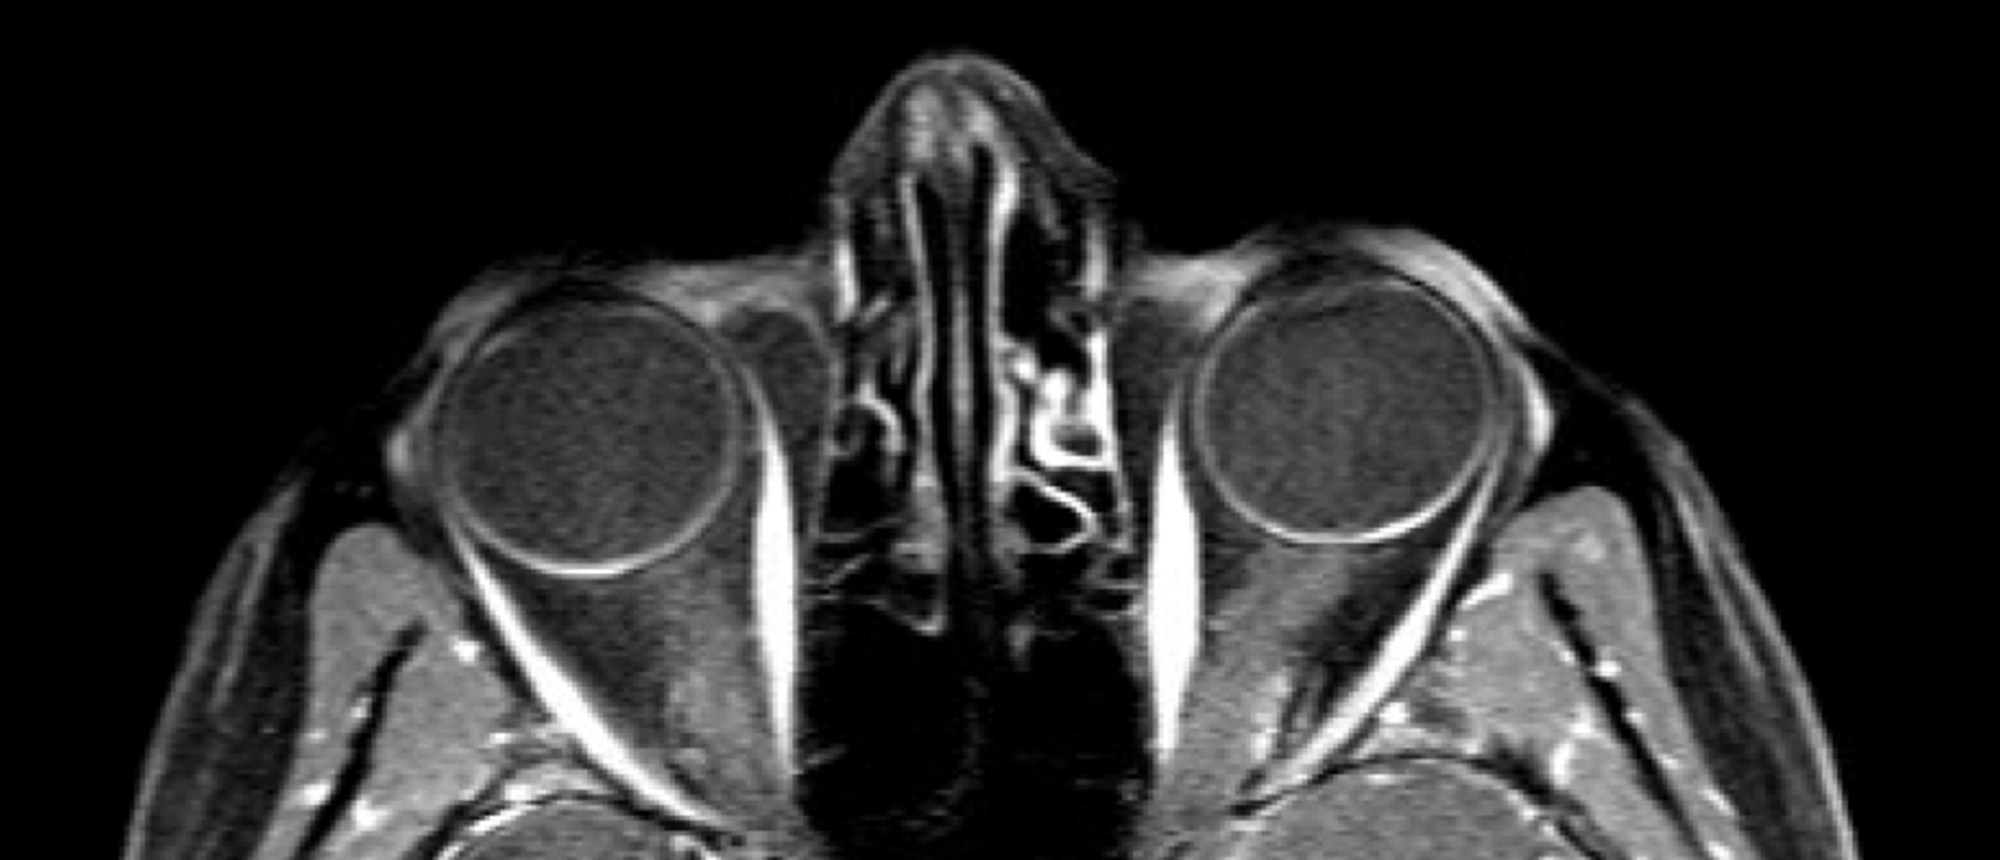

Abstract A patient presented to the Bascom Palmer Eye Institute with blurred vision in the left eye for 5 days. Past medical and ocular history was unremarkable. Past social history was notable for 25 pack-year smoking history. Visual acuity in the right eye was 20/20. Visual acuity in the left eye…

Choroidal Metastasis A patient presented to the Bascom Palmer Eye Institute with blurred vision in the left eye for 5 days. Past medical and ocular history was unremarkable. Past social history was notable for 25 pack-year smoking history. Visual acuity in the right eye was 20/20. Visual acuity in …